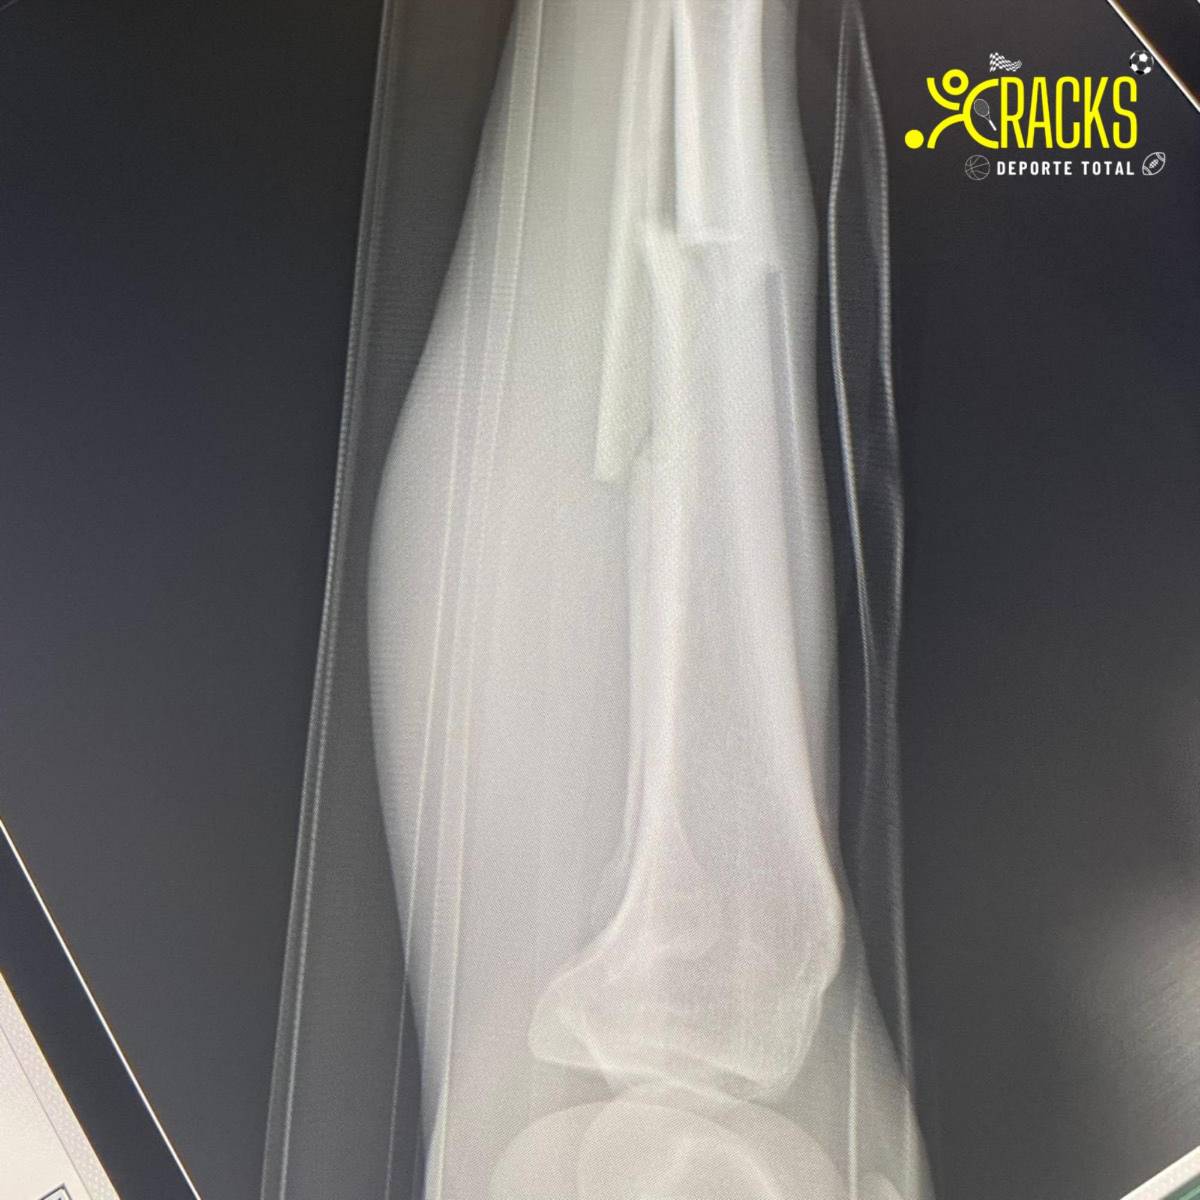

Fuentes al interior de Atlante indicaron que Christian Bermúdez sufrió fractura de tibia y peroné.

“Tras la revisión realizada por el cuerpo médico del equipo al Hobbit, el diagnóstico fue de fractura de tibia y peroné de la pierna derecha.

Christian será sometido a procedimiento quirúrgico”. publicó el club de Liga de Expansión.